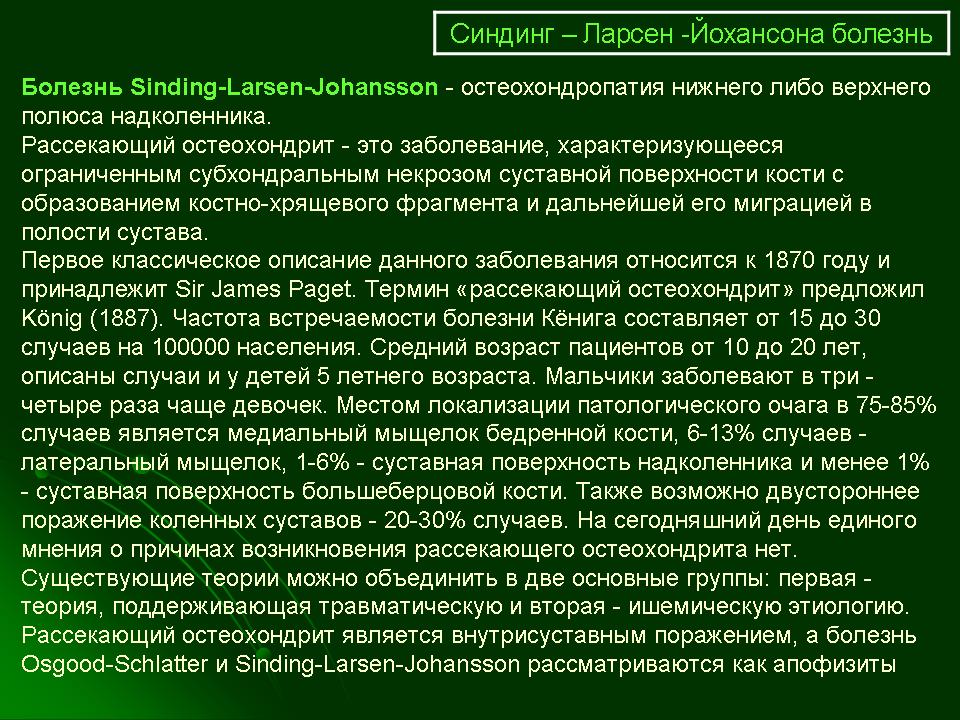

Ларсена йохансона

Ларсена йохансона 146 фото